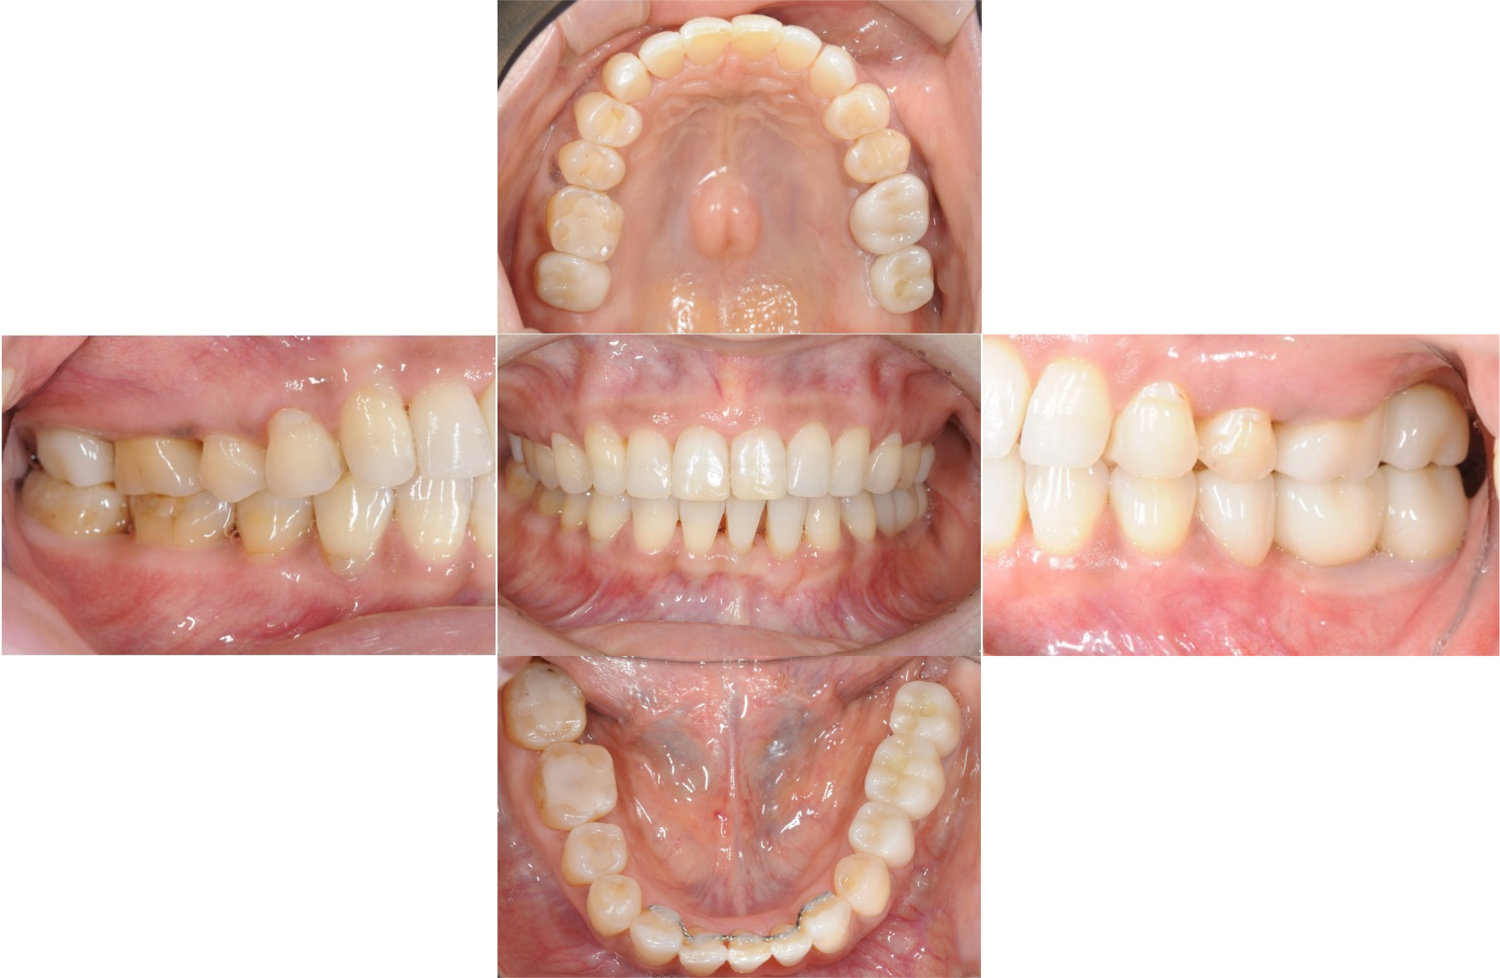

| 主訴 | 全顎治療希望、右下の歯が動いて痛いので噛みずらい。当院でインプラント治療したお母様からの紹介 |

| 治療内容 | プラークコントロール不良なため歯周治療を行い、保存不能の歯を抜歯し、抜歯窩の治癒を待って、欠損部にインプラントを施し咬合再構成を行う。 プロビジョナルレストレーションによる咬合関係を模索した後、全顎にわたりセラミックによる補綴治療、その後メインテナンスに移行 |

| 治療費 | 3,020,000円(税込)(インプラントすべて含む) |

| 治療期間 | 8ヶ月 |

| 治療回数 | 48回 |

| 想定されたリスク | 食いしばり(パラファンクション)によるセラミックの破折、歯の破折 |